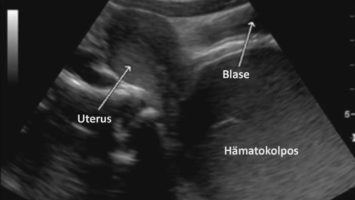

Springer Medizin Podcast - Endometriose/© (M) Willer D. et al. / all rights reserved Springer Medizin Verlag GmbH Logo: Springer Medizin Verlag GmbH, Ärztin misst Blutdruck bei Schwangeren/© Andrey Popov / Stock.adobe.com (Symbolbild mit Fotomodell), Schwangere Frau hält Tablette und Glas Wasser/© NDABCREATIVITY / stock.adobe.com (Symbolbild mit Fotomodell), Justiz/© hawi_101 / Fotolia, CT des Uterus einer 47-Jährigen /© Rizos A et al. | all rights reserved Springer Medizin Verlag GmbH, Gardnerella spp. bedeckte Schlüsselzellen/© Swidsinski A et al. / all rights reserved Springer Medizin Verlag GmbH, Impfung/© Remains / Getty Images / iStock (Symbolbild mit Fotomodellen), Junge Frau sitzt auf Toilette/© Dragana Gordic / stock.adobe.com (Symbolbild mit Fotomodell), Spritze wird aufgezogen/© scyther5 / Getty Images / iStock, Ultraschall der "kissing ovaries" bei Endometriose/© Willer D. et al. / all rights reserved Springer Medizin Verlag GmbH, Ärztin führt Ultraschall bei einer Frau durch/© satyrenko / stock.adobe.com (Symbolbild mit Fotomodellen), Doxy-PEP/© Tobias Arhelger / stock.adobe.com, Junge Frau zur Beratung bei Ärztin/© demaerre / Getty Images / iStock (Symbolbild mit Fotomodellen), Schwangere macht Gymnastik/© fotostorm / Getty Images / iStock (Symbolbild mit Fotomodell), Junge Patientin im Gespräch mit einer Ärztin/© FatCamera / Getty Images / iStock (Symbolbild mit Fotomodellen), Urogenitale Fistel bei einer 36-jährigen Patientin/© Lautenschlager S et al. / exklusiv lizenziert an Springer-Verlag GmbH Austria, ein Teil von Springer Nature 2024, CT bei endometrioidem Karzinom/© Kuzinska MZ et al. / all rights reserved Springer Medizin Verlag GmbH, Frau nimmt Diaphragma in der Hand/© AndreyPopov / Getty Images / iStock (Symbolbild mit Fotomodellen), Ein Abstrich vom Gebärmutterhals wird auf ein Objektivträger geschmiert/© Tatiana Buzmakova / Getty Images / iStock (Symbolbild mit Fotomodellen), Frau nutzt Pen am Bauch/© bung / Stock.adobe.com (Symbolbild mit Fotomodell), Reife Eizelle im Mikroskop/© S. Al-Hasani, Podcast mit Partnern - Roche STI/© (M) Aleksej / stock.adobe.com; Logo: Springer Medizin GmbH, Titelbild Kongress Kompakt EADV 2024/© Hintergrundbild: gnoparus / stock.adobe.com, Search Icon, Paar schaut glücklich auf Schwangerschaftstest/© Andrii Zastrozhnov / Stock.adobe.com (Symbolbild mit Fotomodellen), ZFA TALKS - Depression/© (M) seb_ra / Getty Images / iStock (Symbolbild mit Fotomodell) Logo: Springer Medizin Verlag GmbH, Ältere Frau fasst sich an die Brust/© Jelena Stanojkovic / Stock.adobe.com (Symbolbild mit Fotomodell), Person setzt DNS-Probe in Maschine ein/© Vit Kovalcik / stock.adobe.com